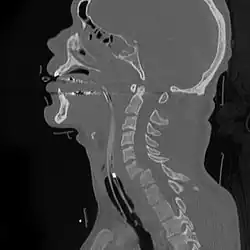

A cervical fracture, commonly called a broken neck, is a fracture of any of the seven cervical vertebrae in the neck. Examples of common causes in humans are traffic collisions and diving into shallow water. Abnormal movement of neck bones or pieces of bone can cause a spinal cord injury, resulting in loss of sensation, paralysis, or usually death soon thereafter (~1 min.), primarily via compromising neurological supply to the respiratory muscles and innervation to the heart.

On CT scan or X-ray, a cervical fracture may be directly visualized. In addition, indirect signs of injury by the vertebral column are incongruities of the vertebral lines,[7] and/or increased thickness of the prevertebral space:[8]

![CT scan of normal congruous vertebral lines[7]](./_assets_/Vertebral_lines.png)